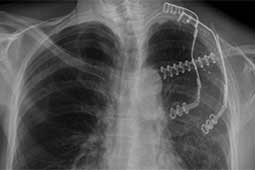

Surgery was performed with curative intent. The patient was positioned supine with the neck fully extended and the head turned away from the tumor. The tumor was approached through the anterior trans-cervical approach described by Dartevelle. This approach allowed us to dissect the subclavian vascular bundle and the nerve roots of the brachial plexus freely, quickly and safely without sacrificing the radical intent of the operation. After assessing the extent of the tumor from inside and outside of the chest, the lateral arches of the first, second and third ribs were cut and removed en-bloc with the surgical specimen (Figure 2). Due to the high risk of de-stabilizing the shoulder girdle after resection of the first three ribs, clavicle division and muscle resection, we reconstructed the chest wall and clavicle using the Stratos™ titanium bars and clips (Strasbourg Thoracic Osteosyntheses System; MedXpert, Heitersheim, Germany) (Figure 3). The chest wall defect and the reconstructed clavicle were covered with polytetrafluoroethylene (PTFE) patches (Figure 4).